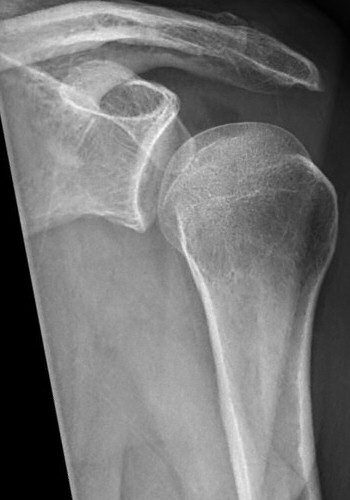

Axelluxation med avlöst tuberkulum majus innan och efter reponering i narkos. Efter reponering förbättrat läge men även misstänkt bony bankart-skada med litet fragment inferiort om glenoiden.